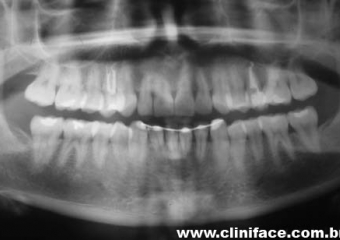

Rx inicial